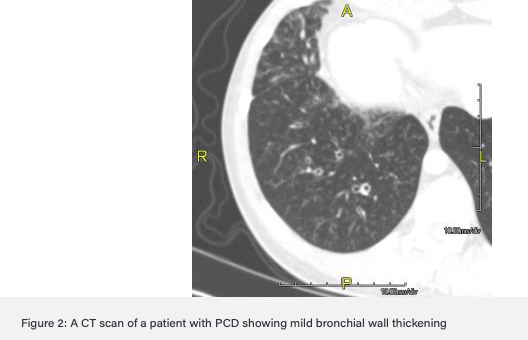

What signs are indicative of bronchiectasis on HRCT in children?

• Bronchial wall thickening

• Diameter of bronchus larger than bronchial artery next to it (Signet Ring)

• Visible peripheral bronchi

Different patterns different aetiologies

• Bilateral upper lobe bronchiectasis commoner in CF

• Unilateral upper lobe bronchiectasis commoner post-TB infection

• Focal bronchiectasis (lower lobe) after foreign body inhalation